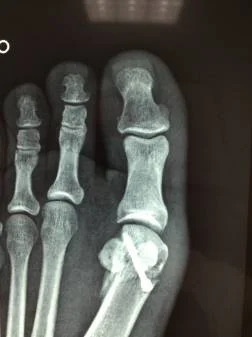

Caso clínico: Hallux Valgus

Preoperatorio

Radiografia preoperatoria

Paciente femenino de 32 años, portadora de hallux valgus doloroso en el pie derecho. Intervenida quirúrgicamente por el Dr Alberto Martínez Conde, practicandole cura operatoria con osteotomia del primer metatarso según técnica de Chevron y fijación con tornillo de Bold de 3.0 mm.